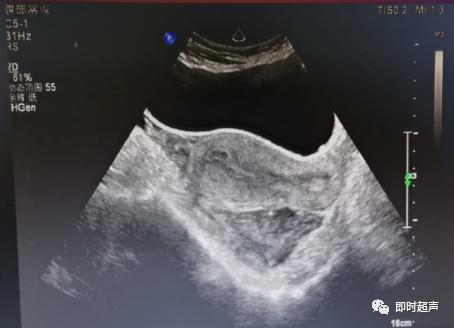

超声下腹腔大量液性暗区,扫查发现左侧附件区一孕囊样回声,其内可见似胚芽组织,CDFI:未见明显血流信号,考虑:1.左侧附件区异位妊娠2.盆腔大量液性暗区,性质待定。建议HCG检查。

血压120/80mmHg,插导尿管,查尿HCG(+),确定怀孕。随后完善各项检查,行急诊开腹手术,发现左侧输卵管壶腹部一大小约29×35mm包块,与B超数据相吻合。确定盆腔积液为大量血液,量约1800ml。患者各项生命体征平稳,转危为安。